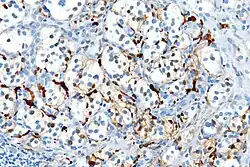

Several members of the S100 protein family are useful as markers for certain tumors and epidermal differentiation. They can be found in melanomas,[8] 100% of schwannomas, 100% of neurofibromas (weaker than schwannomas), 50% of malignant peripheral nerve sheath tumors (may be weak and/or focal), paraganglioma stromal cells, histiocytoma, and clear-cell sarcomas. Further, S100 proteins are markers for inflammatory diseases and can mediate inflammation and act as antimicrobials.[9] S100 proteins have been used in the lab as cell markers for anatomic pathology.